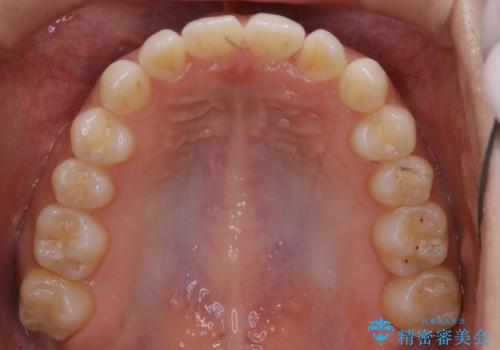

- 前から2番目の歯が捻じれていることが気になるとご相談にいらした方です。

インビザラインFULLで治療を行いました。

上の前から2番目の歯は、一般的に周囲の歯と比べて小さく、動きづらい歯であると言われています。前歯にゴムかけを行うことで理想的な位置まで歯を動かしてくることが出来ました。